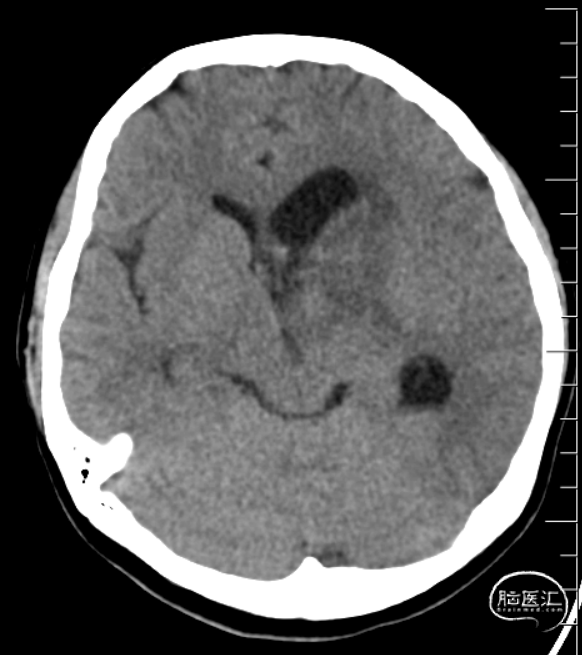

术后第1天CT(患者术后6小时自行拔除引流管)

术后第3天磁共振